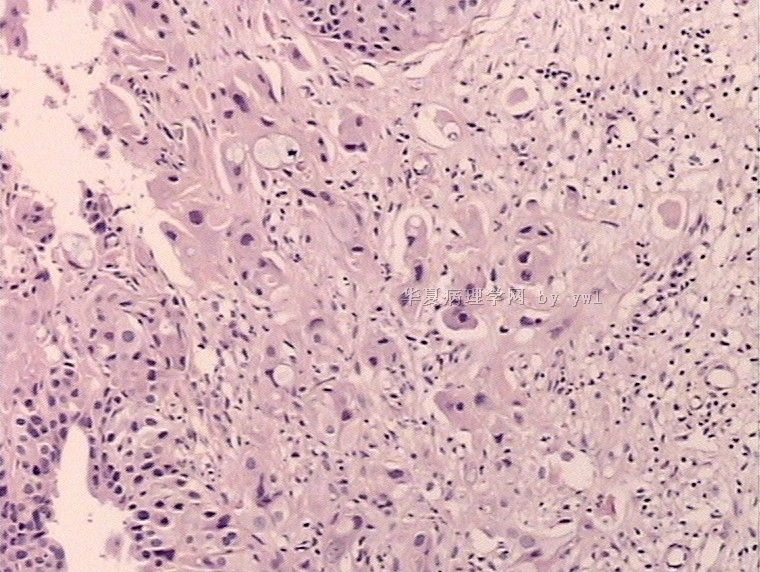

腺鳞癌?

姓    名: ××× 性别:   年龄:  39岁

标本名称:  宫颈活检

简要病史:  同房出血3次,tct HSIL

考虑:原位腺癌,小灶性区域有鳞状上皮向间质内浸润,考虑有鳞状细胞癌结构。

• 腺鳞癌?图1

图1